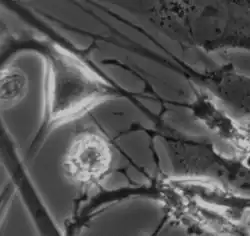

The myenteric plexus from the rabbit. X 50.

The myenteric plexus from the rabbit. X 50.